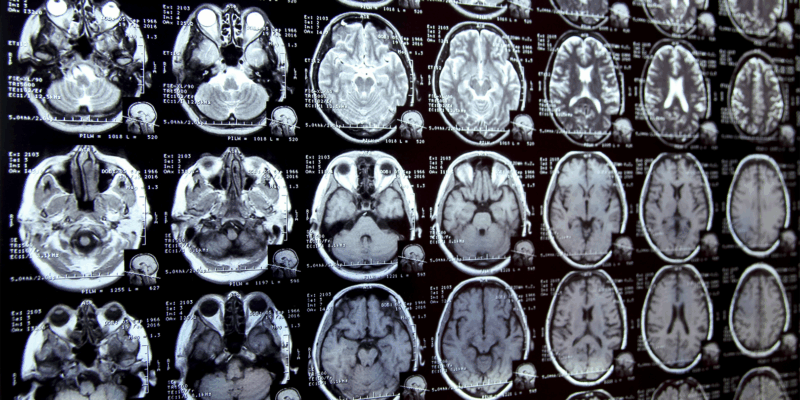

Der mühsame Prozess der Segmentierung - oder Kommentierung - bestimmter Bereiche in medizinischen Scans spielt bei vielen biomedizinischen Forschungsprojekten eine entscheidende Rolle. Ob bei der Untersuchung von Veränderungen in Gehirnstrukturen wie dem Hippocampus oder bei der Verfolgung des Fortschreitens einer Krankheit - Forscher müssen diese Regionen oft mühsam von Hand umreißen. Diese Methode kann besonders mühsam sein, vor allem wenn die Strukturen, die sie in den komplexen medizinischen Bildern hervorheben wollen, schwer zu unterscheiden sind.

Stellen Sie sich vor, wie es wäre, eine Studie darüber durchzuführen, wie sich der Hippocampus des Gehirns mit dem Alter verändert. Ein Forscher müsste in der Regel den Hippocampus auf unzähligen Gehirnscans durchforsten und mühsam umreißen. Glücklicherweise hat eine Gruppe von Forschern des MIT eine spannende Lösung für dieses Problem gefunden.

Um diesen Herausforderungen zu begegnen, hat das MIT-Team Folgendes entwickelt MultiverSegein ausgeklügeltes KI-basiertes System, das den Prozess der Bildsegmentierung viel schneller und benutzerfreundlicher machen soll. Mithilfe von Eingaben wie Klicks, Kritzeleien und Begrenzungsrahmen können die Nutzer Bilder interaktiv kommentieren. Je mehr Bilder mit Anmerkungen versehen werden, desto mehr lernt das KI-Modell aus diesen Interaktionen und reduziert den Bedarf an weiteren Eingaben, bis es schließlich neue Bilder selbstständig segmentieren kann.